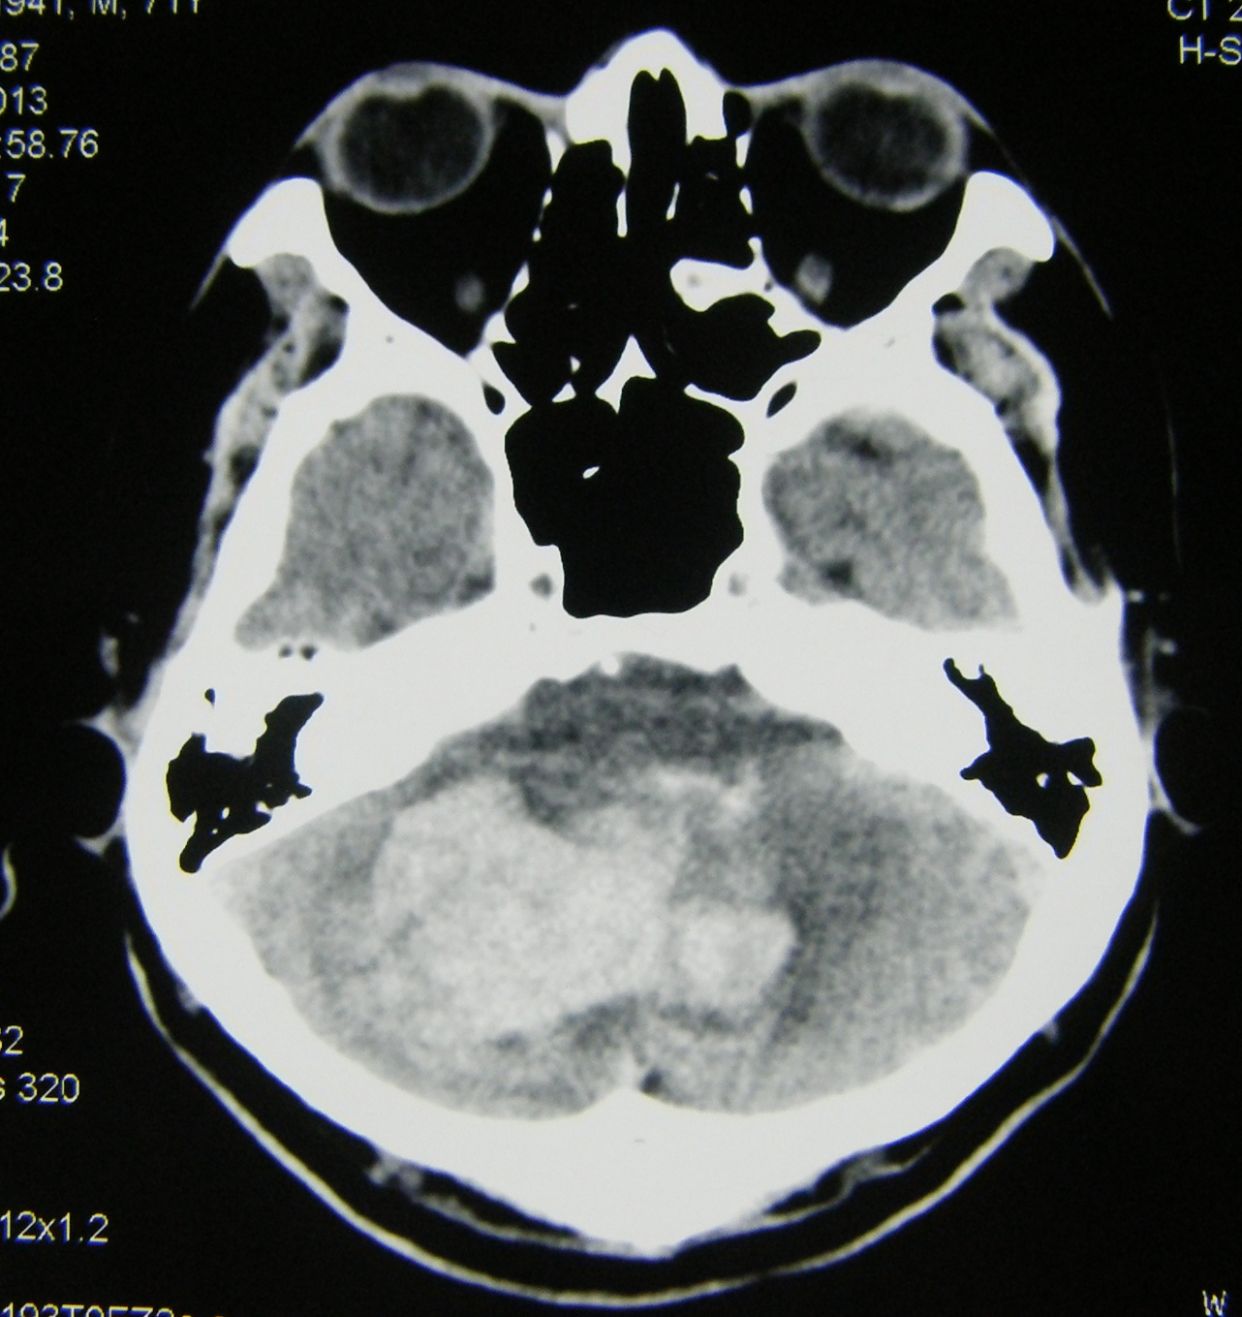

例1,患者男,70岁,突发意识不清1小时入院,有高血压等病史多年,深昏迷状,入院查体时出现呼吸停止,双瞳孔散大,立即气管插管,人工呼吸,建立静脉通道,应用甘露醇等。

CT显示小脑大量出血并破入全脑室,梗阻性脑积水,脑干受压变形,与家属沟通并签字后,急症行脑室引流术,后颅凹开颅血肿清除术,气管切开术。